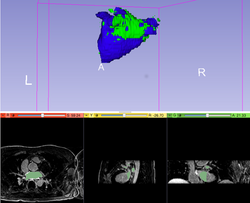

Slicer4 Quantitative Imaging tutorial

- The Slicer4 Quantitative Imaging tutorial guides through the use for Slicer for quantifying small volumetric changes in slow-growing tumors, and for calculating Standardized Uptake Value (SUV) from PET/CT data.

- Authors: Sonia Pujol, Ph.D., Katarzyna Macura, M.D., Ron Kikinis, M.D.

- Audience: Radiologists and users of Slicer who need a more comprehensive overview over Slicer4 quantitative imaging capabilities.

- Modules: Data, Volumes, Models, Change Tracker, PET Standard Uptake Value Computation

- Based on: 3D Slicer version 4.5

- The Quantitative Imaging dataset contains a series of MR and PET/CT data.